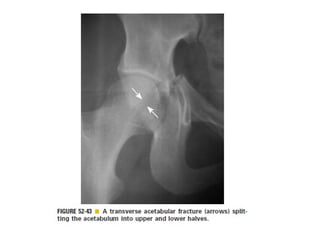

Skeletal trauma was presented by Dr Laith Fadhel with reference to Grainger's Diagnostic Radiology textbook. The presentation covered skeletal trauma as assessed through diagnostic radiology techniques. Key findings and treatments for skeletal injuries were likely discussed.